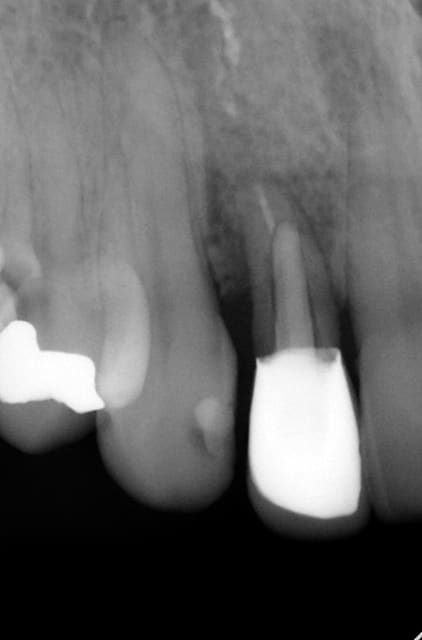

- Perforation vestibulaire ..toujours vérifier l'intégrité du forage à la sonde.. si il y a perforation ne pas placer l'implant ..Il faut noter que l'effet dilatateur de l'implant peut entrainer l'effraction vestibulaire mais là en principe le maintien du périoste est un allié.

- déviation..Parfois la corticale est tellement résistante que malgré un forage initial parfait l'implant au vissage est dévié. On n'a pas ce problème avec l'utilisation de foret cylindrique coupant dans le cas de la chirurgie MIMI l'effet ostéotome peut entrainer ce type de surprise

1/ implant premo pas assez angulé/concavité vestibulaire (prep cap droit) .. en plus négligence personnelle pas de controle à la sonde...en plus patiente hyper stress..elle a eu mal + tuméfaction..elle a refusé que je tente la pose d'une membrane ..dépose de l'implant..regle des 3 R : rassurer remplacer rembourser. :(